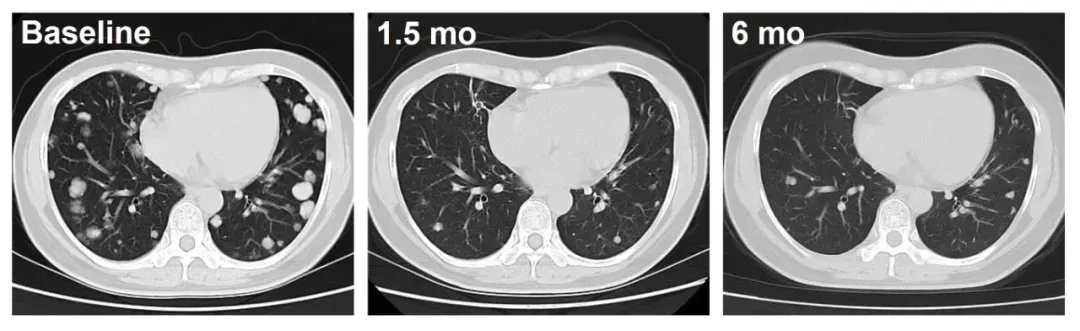

其针对经1-6线治疗失败的晚期肝癌(HCC)的IIT临床数据显示:两例患者(C023、C010)治疗后均实现肿瘤持续退缩的振奋疗效:患者C010(DL3)随访超12个月,肿瘤持续稳定缩小;患者C023(DL4)治疗1.5个月后,肺转移病灶深度应答,影像学可见肿瘤显著缩小(详见下图)。

▼C023号患者治疗前后影像学对比

▼C010号患者治疗前后影像学对比